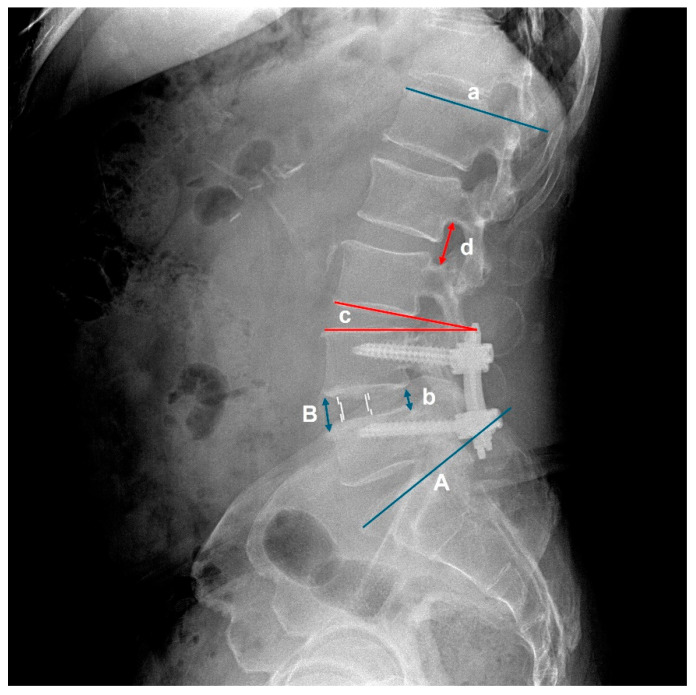

Background: Oblique lumbar interbody fusion (OLIF) has recently gained popularity as a minimally invasive surgical technique for lumbar fusion. While OLIF is superior in restoring disc height and lumbar lordosis compared to posterior lumbar interbody fusion (PLIF), its biomechanical effect on adjacent segments remains unclear. Methods: We retrospectively analyzed 236 patients who underwent one- or two-level OLIF (n = 95) or PLIF (n = 141) between 2013 and 2020. Radiographic outcomes, including lumbar lordosis, upper adjacent segmental lordosis, retrolisthesis, and foraminal height, were evaluated preoperatively and at 3 days and 1, 3, 6, and 12 months postoperatively. Patient-reported outcomes (VAS for back/leg pain and Oswestry Disability Index [ODI]) were assessed preoperatively and at 12 months. Results: OLIF provided superior restoration of lumbar lordosis (4.03 ± 4.38° vs. 1.63 ± 5.11°, p = 0.001) and disc height (5.50 ± 3.39 mm vs. 2.71 ± 2.18 mm, p < 0.0001) compared with PLIF. However, OLIF was associated with higher incidence (76.9% vs. 24.6%, p < 0.0001) and degree of retrolisthesis (1.69 ± 1.09 mm vs. 0.29 ± 0.70 mm, p < 0.0001), and decreased foraminal height (-1.43 ± 2.12 mm vs. 0.54 ± 2.53 mm, p < 0.0001) in the upper adjacent segment. Importantly, there was no significant difference in clinical outcomes (VAS and ODI) between the two groups at 12 months (all p > 0.05). Conclusions: While OLIF achieves superior restoration of lumbar lordosis and disc height compared to PLIF, it also induces early radiographic deterioration in the upper adjacent segment. Importantly, these findings represent radiographic changes observed within 1 year, without significant differences in clinical outcomes, and longer-term follow-up is required to determine their clinical relevance.